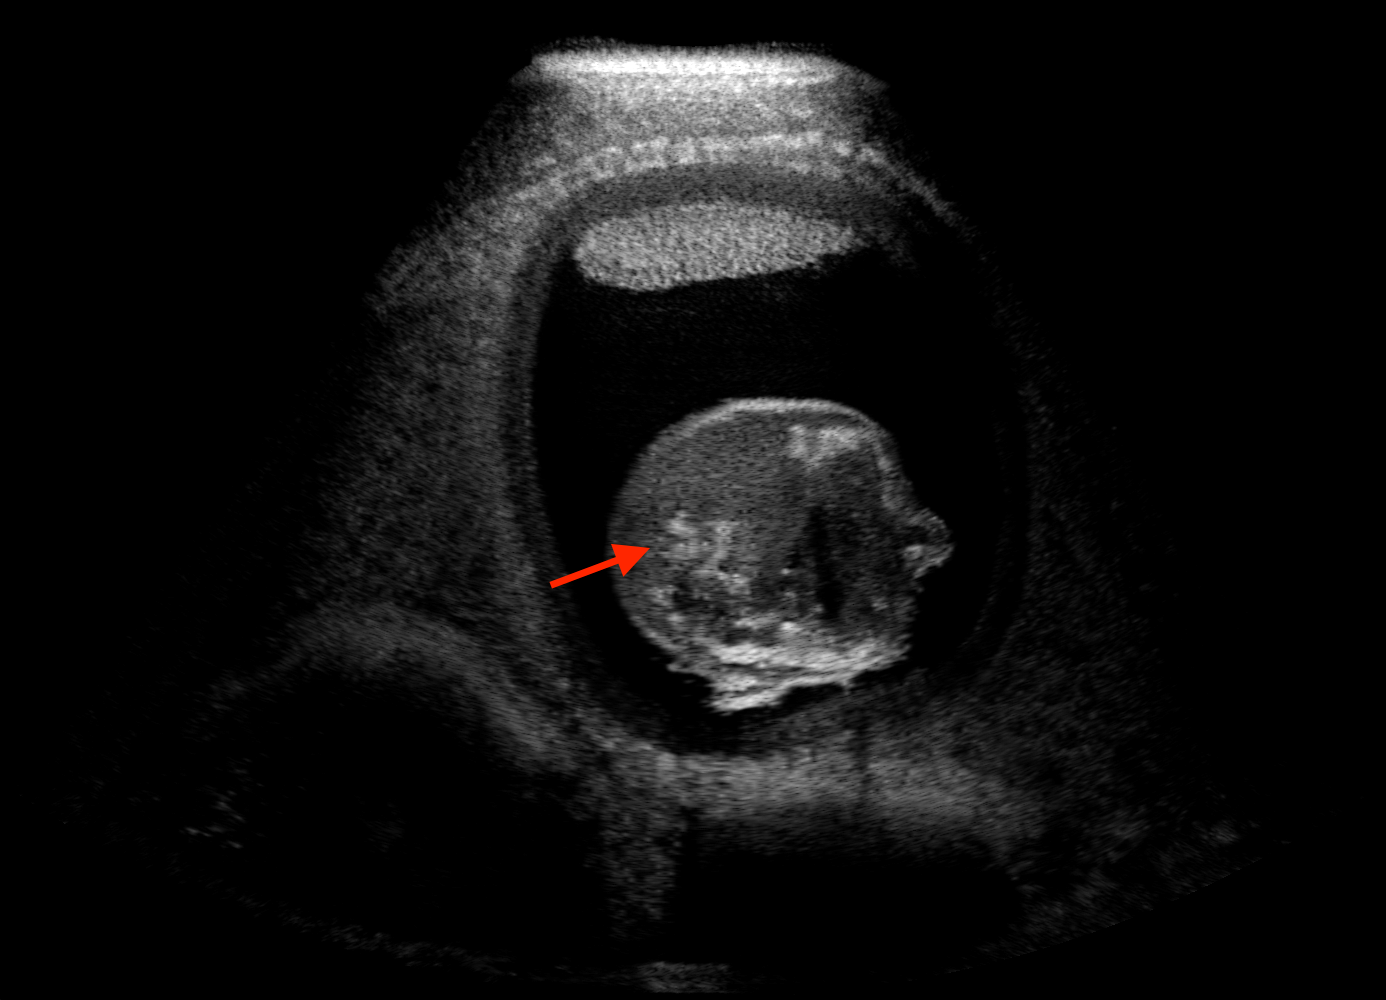

For the interpretation of the local errors, sample spatial p error maps are depicted in Fig. 3 for LSA2H, NSA2H, and SA2H for the middle two examples shown in Fig. 2. Both images generated by NSA2H have a lot of missing structures and accordingly have high error almost all over the map. Artificial skull enhancement with LSA2H is seem to evoke large p error, as shown in the corresponding error map, whereas the bright spots in the error map of SA2H reflect some hallucinated shadows and structure in the brain. All of above mentioned regions of interest are marked by red arrows. In the bottom example, SA2H fails to generate faithful content at the bottom region marked by red circles, which is well indicated by the error map as well.